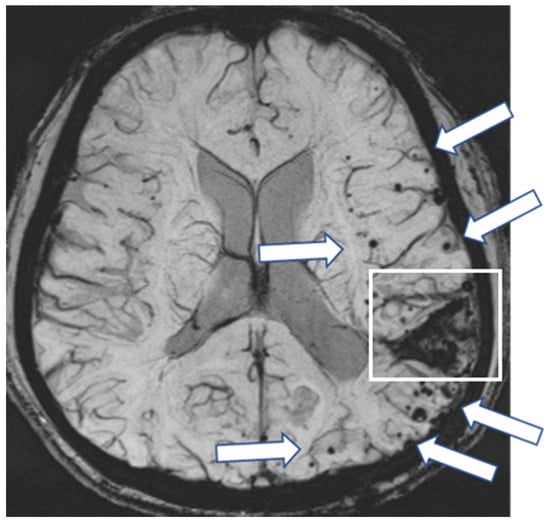

A 56-year-old man presented with sensory and motor disturbances in his left hand, which subsequently improved without specific treatment. At the age of four, he suffered a traumatic brain injury in a car accident that required cranial surgery at the right parietal region. Cadaveric dura mater use was not confirmed. He had no history of hypertension or familial CAA. CT showed lobar ICH in the right cerebral hemisphere, and SWI showed multiple lobar CMBs and cSS in both cerebral hemispheres (Figure 4). The CAA-SVD score was 6 based on the previous literature [5], consisting of two points for lobar CMBs, two points for cSS, one point for CSO-PVSs, and one point for WMH. Notably, cSS was also observed in the right postcentral gyrus, which may be associated with TFNEs. Contrast-enhanced 3D FLAIR showed enhancement in the sulci of the bilateral occipital lobes while enhancement was not detected on the contrast-enhanced 3D GRE T1-weighted image. Neither CSF examination nor amyloid PET was performed. Thus, this case was considered a possible iCAA based on the criteria [1].

Figure 4.

(a) SWI shows lobar hemorrhages (square) in both cerebral hemispheres, multiple lobar CMBs (arrows), and cortical superficial siderosis (cSS) (arrow heads). cSS in the right postcentral gyrus may be associated with TFNEs; (b) non-contrast 3D FLAIR shows postoperative changes in the right parietal lobe (circle); (c) contrast-enhanced 3D FLAIR shows sulcal enhancement in the bilateral occipital lobes (small arrows) while enhancement was not detected on (d) the contrast-enhanced 3D GRE T1-weighted image.